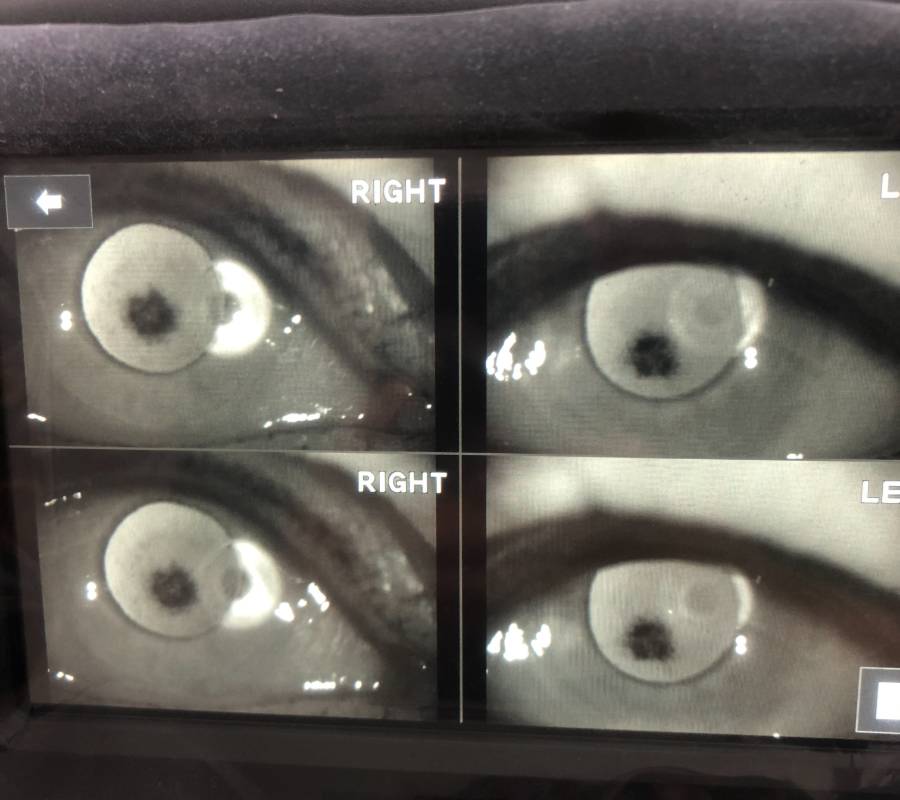

Pemeriksaan menyeluruh ke atas bahagian hadapan (anterior) dan belakang (posterior) mata—termasuk kornea, kanta, iris, retina serta saraf optik.